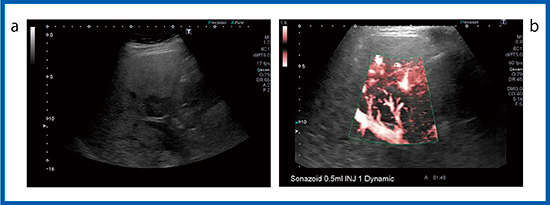

図9は,膵NETの肝転移症例である。造影SMI(図9 a)ではリング状の染まりがありその内部に血流が見られるが,SWEでは,カラーマップ表示されなかった(図9 b)。腫瘍の部分に剪断波が生じていないことから,肝転移のような硬い組織の場合,プッシュパルスでは剪断波が発生しない可能性が示唆された。また,浅部側は多重反射などのアーチファクトがあるほか,深部側や横隔膜近傍のS8はカラーマップ表示が難しい場合がある。

図9 膵NETの肝転移のSWE

a:造影SMI b:SWE